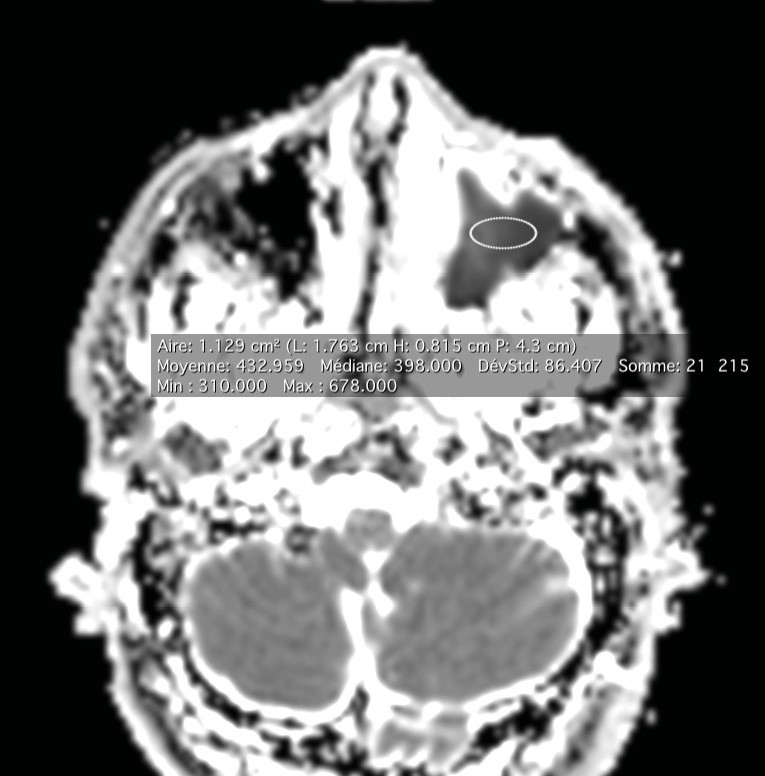

La tomodensitométrie des sinus retrouve un comblement complet unilatéral du sinus maxillaire gauche et des cellules ethmoïdales antérieures homolatérales, sans image de densité calcique intrasinusienne et sans lyse osseuse des parois (fig. 1). L’IRM montre un épaississement tissulaire de 23 mm de grand axe en regard du méat moyen gauche, avec un aspect de signal T2 hétérogène (fig. 2) et prenant le contraste en masse (fig. 3). Le comblement maxillaire gauche associé à un épaississement muqueux en cadre rehaussé correspond à une rétention en hypersignal en diffusion (fig. 4), avec diminution du coefficient apparent de diffusion (moyenne à 433 mm2/s) en faveur d’une pyocèle (fig. 5).